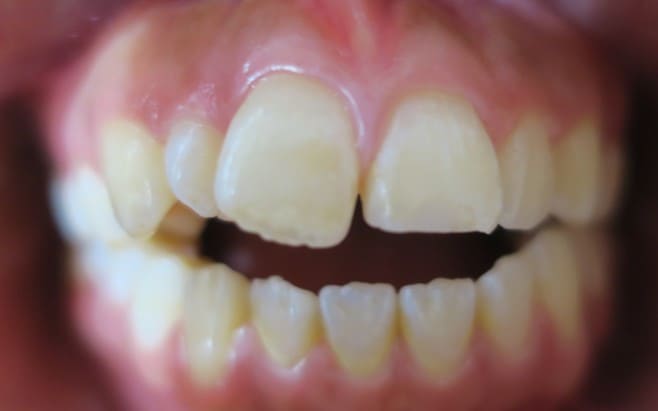

藤沢デンタルオフィスのホワイトニング術前

藤沢デンタルオフィスのホワイトニング術後

藤沢デンタルオフィスのホワイトニング術前 藤沢デンタルオフィスのホワイトニング術後

術前

術後